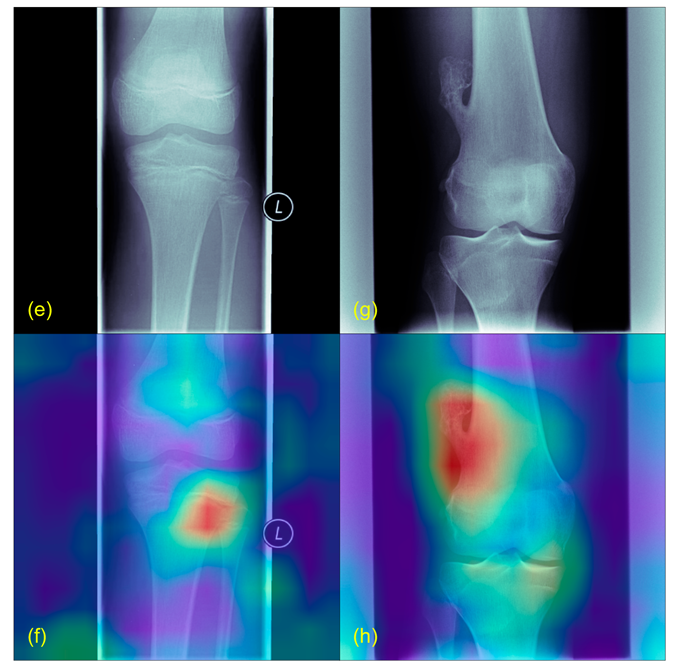

- Selvaraju, R.R.; Cogswell, M.; Das, A.; Vedantam, R.; Parikh, D.; Batra, D. Grad-CAM: Visual Explanations from Deep Networks via Gradient-Based Localization. Int. J. Comput. Vis. 2020, 128, 336–359. [Google Scholar] [CrossRef]